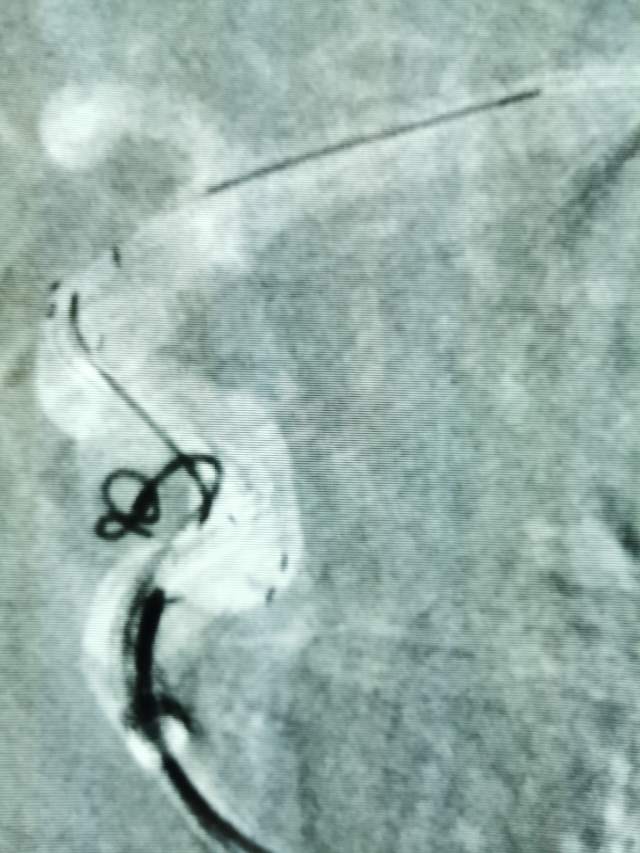

Jailing技术治疗床突旁未破裂动脉瘤